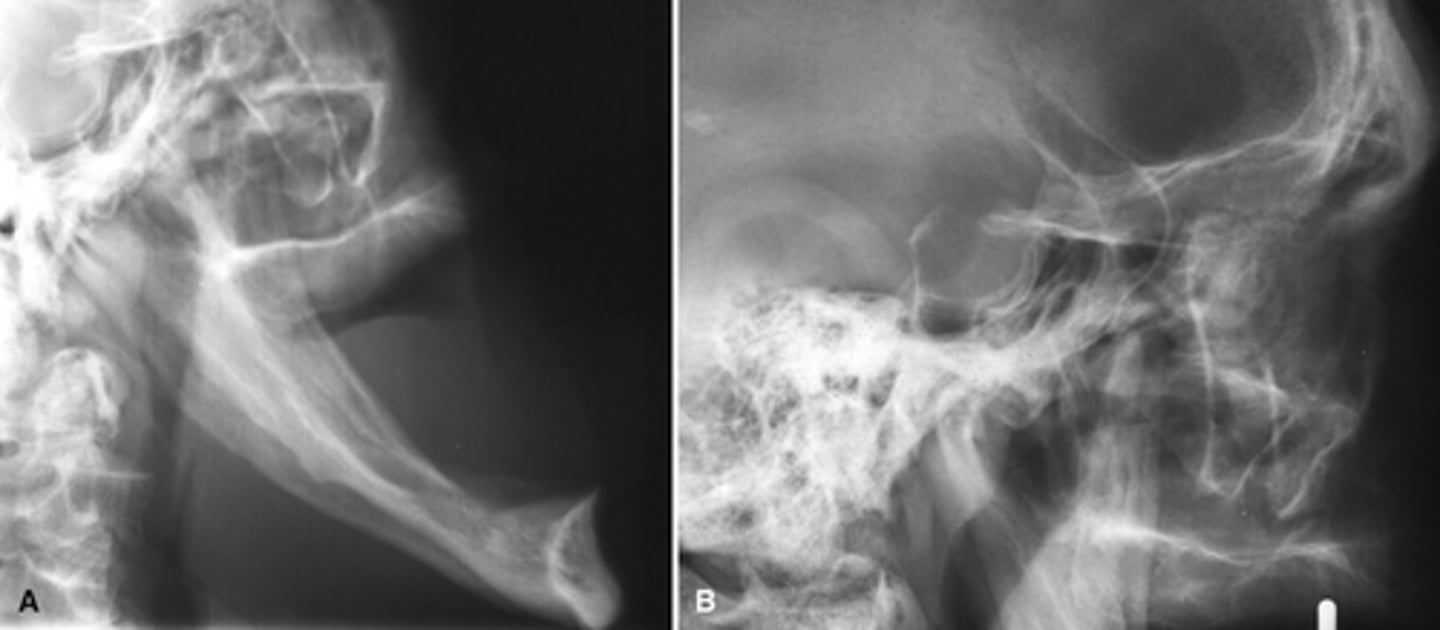

RA (rheumatoid arthritis)

Image A shows a lateral ceph where the patient has a steep mandibular plane and anterior open bite.

Image B shows erosion of the temporal component of the TMJ

What is the diagnosis of the patient based off these radiographs and what are the features?